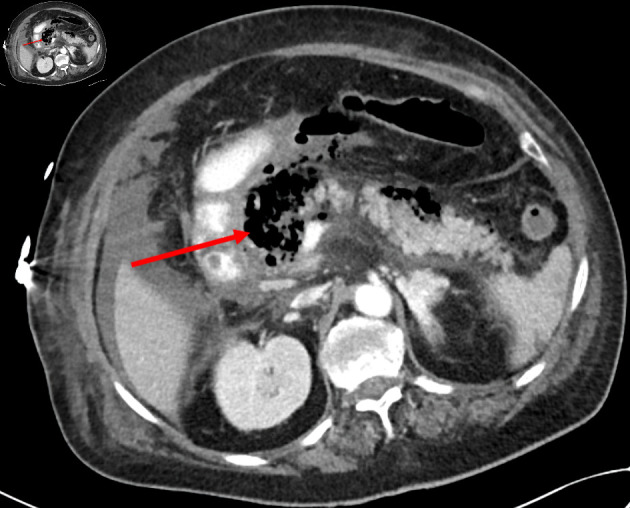

气肿性胰腺炎(EP)是一种严重的胰腺坏死性感染,是一种极为罕见的急症,死亡率很高。其特点是胰腺实质内或胰腺周围充气,原因是单微生物或多微生物感染产气细菌,或者是肠胰瘘。急性胰腺炎根据计算机断层扫描(CT)发现气泡征象的起病时间分为早期起病(起病两周内)和晚期起病(起病两周以上)。虽然大多数急性胰腺炎病例仅通过支持性治疗即可缓解,但 EP(尤其是早发亚型)的临床预后非常差,发病率和死亡率都很高。这两份病例报告介绍了我院收治的两名早发暴发性急性胰腺炎患者的临床特征、诊断检查和治疗情况,他们分别接受了不同的检查和治疗。第一例患者接受了更为保守的治疗,在入院 52 小时后才确诊,因此推迟了入住重症监护室(ICU)和手术的时间;而第二例患者在发病数小时后才确诊,并提前入住重症监护室。在本文中,我们将介绍早期诊断上述罕见重症胰腺炎的重要性,并探讨快速诊断对病程、发病率和死亡率的影响。

Emphysematous pancreatitis (EP), a severe form of necrotizing infection of the pancreas, is an extremely rare medical emergency with high rates of mortality. It is characterized by intraparenchymal pancreatic or peri-pancreatic air due to either monomicrobial or polymicrobial infection with gas-forming bacteria or due to entero-pancreatic fistula. EP is classified according to timing from disease onset when air bubble signs were detected on computed tomography (CT) scan, as early onset (within 2 weeks from disease onset) or late (more than 2 weeks from disease onset). While most cases of acute pancreatitis are resolved with supportive care alone, clinical outcomes of EP, especially the early onset subtype, are very poor with high rates of morbidity and mortality. These two case reports present the clinical features, diagnostic investigations, and management of two patients admitted to our hospital with early onset fulminant EP, each investigated and managed with different approaches. The first patient underwent a more conservative treatment, with diagnosis being made 52 h following admission, and thus, intensive care unit (ICU) admission and surgery were postponed, while the second patient was diagnosed a few hours following presentation with earlier ICU admission. In this article, we will present the critical importance of early diagnosis of the aforementioned rare entity of severe pancreatitis and will consider the consequences of rapid diagnosis on disease course, morbidity and mortality.